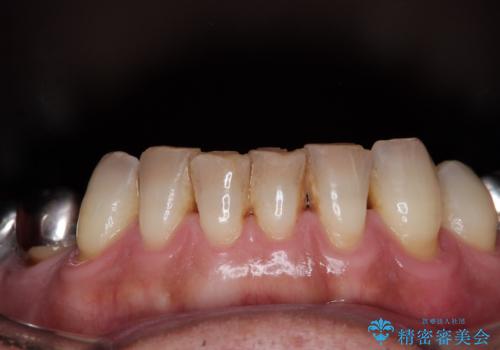

黄ばんだ前歯をきれいに 前歯の審美歯科治療

- 薬剤の影響で黄ばんでしまった前歯を気にして来院された患者様です。

奥歯の銀歯も気にはなるものの、口を開けたときに目立たないとのことで、上下ともに前歯を中心にオールセラミッククラウンにて補綴治療を行うこととしました。